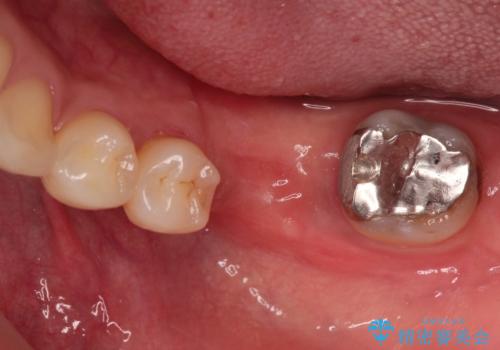

見えない歯周病 長期予後を見据えてインプラントに

- Ⅲ度の分岐部病変をきたした第1大臼歯を抜去、待時しインプラントによる咬合回復を計画した。

インプラントの種類:strauman SLActive

かぶせ物の種類:Bellezza screw retain